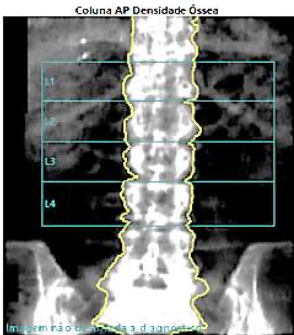

Sobre o exame a seguir pode-se afirmar:

Assinale a alternativa correta.